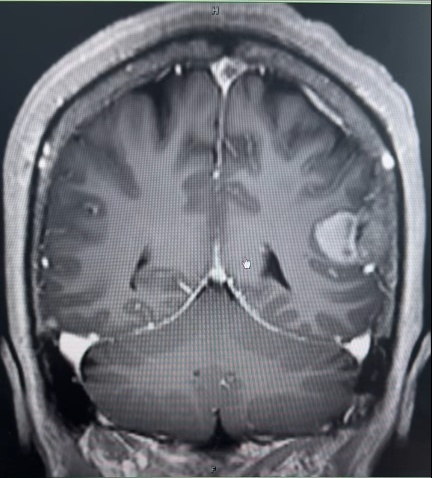

在青海大学附属医院,另一例颅内肿瘤手术同样面临挑战。该患者术前影像考虑脑膜瘤,尽管肿瘤体积不大,但肿瘤位置特殊——位于左侧顶叶,运动区附近,血运丰富,患者术前肢体已有症状,一旦损伤可造成严重的并发症。王虎主任与当地专家术前经过充分的讨论与准备,制定了完善的手术方案。

术中,王虎主任最终仅用时2小时就将肿瘤全部切除,并且术后未造成任何并发症,不仅解决了患者的难题,也促进了两院的合作。